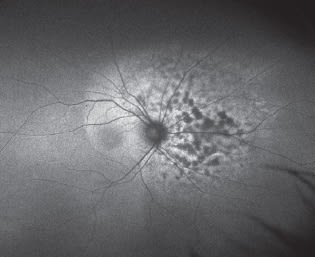

Image courtesy of Optos

Shown is an ultra-widefield fundus autofluorescence image of a choroidal melanoma extending into the peripheral retina.